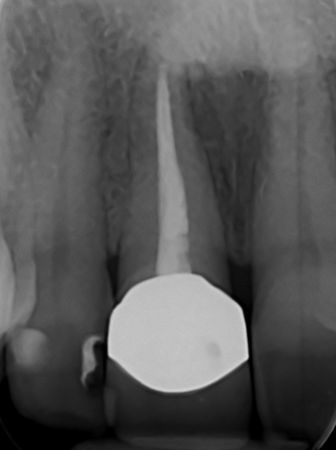

The main issue involved the upper right central incisor (tooth 1.1), which was devitalized and presented recurrent abscesses. Clinical and radiographic evaluation confirmed the presence of buccal bone wall resorption, leading to a significant defect in the alveolar ridge. This condition compromised both the hard tissue and the surrounding soft tissue, posing a challenge for achieving long-term stability and esthetic success in the anterior maxilla.

The surgical protocol began with the atraumatic extraction of tooth 1.1 to preserve as much of the alveolar socket as possible. Immediately following extraction, an N1 implant was placed into the socket using a guided surgical approach to ensure ideal three-dimensional positioning. The “one abutment one time” technique was applied to minimize soft tissue manipulation during the healing phase, which is particularly important in esthetic areas.